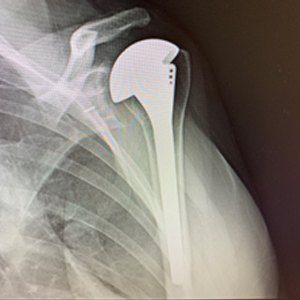

X-ray After